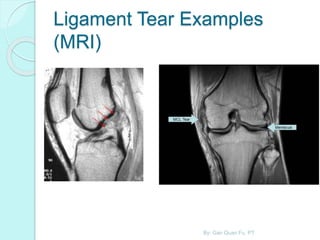

Joints Tendon and Ligaments

 Most accurate examination available

for joints and the surrounding tendons,

ligaments and cartilage.

 Helpful for sports related injuries.

By: Gan Quan Fu, PT

Ligament Tear Examples

(MRI)